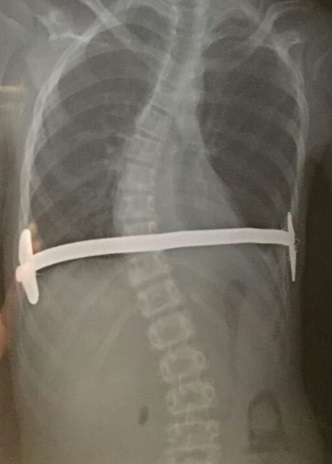

其次,钢板两端形状的问题(图2,3,4)。钢板放入体内前,要对钢板进行满意的塑形,使之不但能起到支撑或者压迫的作用,还要与胸廓自然形状相适应,不能使两端翘得太高。两端翘得过高,皮肤表面就可能被顶起来。当皮肤被衣服或者外界因素摩擦时,可能轻易被磨破而导致钢板外露。

图4,该患者的钢板放置比较贴体,不容易露出体表。